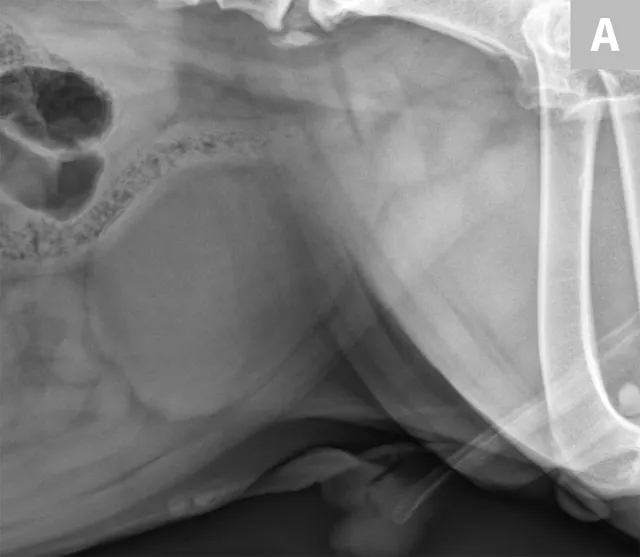

FIGURE 6A

Mild to moderate right hydronephrosis and proximal ureteral dilation in a Dalmatian.